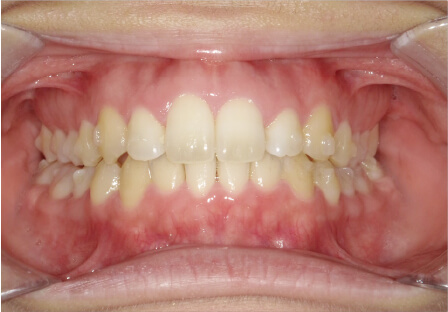

叢生の症例

28歳

/

女性

相談内容

カウンセリング・診断結果

IPR承諾、アレルギー無

治療内容・方法

全顎アライナー矯正

術後の経過・現在の様子

クリアライナー使用

治療のリスク

痛み・歯根吸収・歯肉退縮・虫歯・後戻り

費用・治療期間

990,000円、3年

トレーニングなど